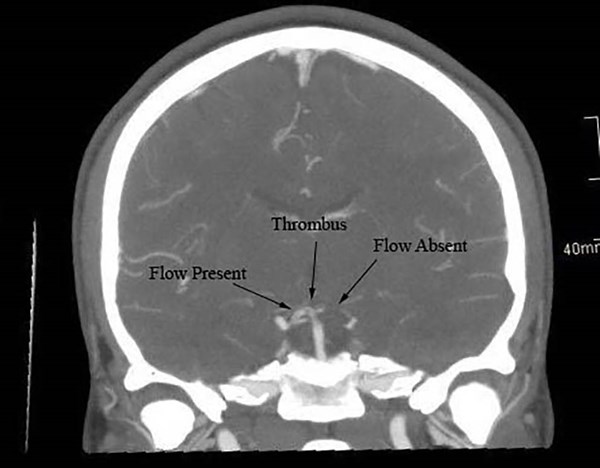

These findings were concerning for a vertebral artery dissection. Additionally, CT angiogram of the head showed partial thrombosis of the distal basilar artery and an occlusive thrombus extending into the left superior cerebellar artery (Figure 2).

Figure 2. CT angiogram of the head